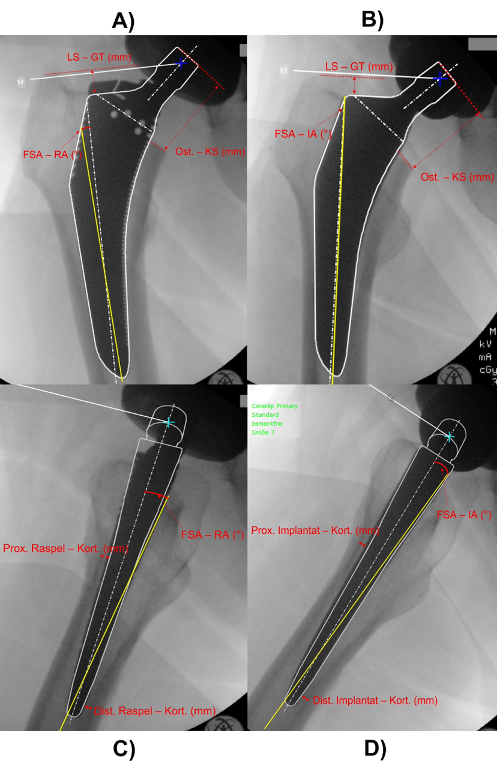

Material und Methoden: Anonymisierte Röntgenaufnahmen (koronal/sagittal) von 50 Patient:innen (Alter 62,9 ± 16,6 Jahre), die eine zementfreie primäre HTEP über den direkten anterioren Zugang (DAA) erhielten, wurden retrospektiv analysiert. In prä- und postoperativen Röntgen-Beckenübersichtsaufnahmen wurden femorale Version, Osteotomiehöhe, Cortical Thickness Index (CTI) und Beinlängendifferenz (BLD) vermessen. Intraoperative Messungen umfassten den Winkel zwischen Raspel- und Implantatachse sowie der Femurschaftachse (FSA) in Koronar- und Sagittalebene. Zusätzlich wurden in der Koronarebene der Abstand von Raspel- bzw. Implantat-Schulter zu Trochanter major und Osteotomie–Konusspitze gemessen. In der Sagittalebene bestimmten wir die minimalen Abstände von Raspel bzw. Implantat zur Kortikalis. Abschließend analysierten wir die Positionsdifferenzen (FFR-FFI). Alle Messungen erfolgten in mediCAD® V7.0 (mediCAD Hectec GmbH, Altdorf, Deutschland).

Abbildung 1 [Abb. 1]

Abbildung 1: Intraoperative Messungen in Koronar- und Sagittalebene. (A) Raspel, (B) Implantat in Koronarebene; (C) Raspel, (D) Implantat in Sagittalebene. IA = Implantatachse; RA = Raspelachse; Kort. = Kortikalis; Prox. = Proximal; Dist. = Distal; Ost. = Osteotomie; KS = Konusspitze; LS = Laterale Schulter; GT = Trochanter major.